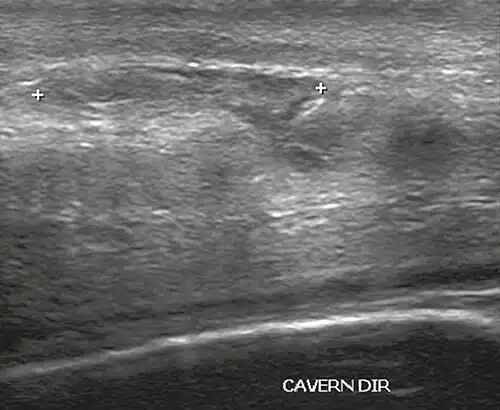

In the ultrasound examination, a lesion of the tunica albuginea presents as an interruption in (loss of continuity of) the echoic line representing it (Figure 4). Small, moderate, or broad hematomas demonstrate the extent of that discontinuity. Intracavernous hematomas, sometimes without the presence of a tunica albuginea fracture, can be observed when there is a lesion of the smooth muscle of the trabeculae surrounding the sinusoid spaces or the subtunical venular plexus.[2]

![Figure 4 A: Ultrasound of the penis, right lateral view. Longitudinal section showing rupture of the tunica albuginea with an adjacent 1.92 cm hematoma (between calipers), due to trauma.[2]](./_assets_/Ultrasonography_of_ruptured_tunica_albuginea.jpg) Figure 4 A: Ultrasound of the penis, right lateral view. Longitudinal section showing rupture of the tunica albuginea with an adjacent 1.92 cm hematoma (between calipers), due to trauma.[2] Figure 4 A: Ultrasound of the penis, right lateral view. Longitudinal section showing rupture of the tunica albuginea with an adjacent 1.92 cm hematoma (between calipers), due to trauma.[2]